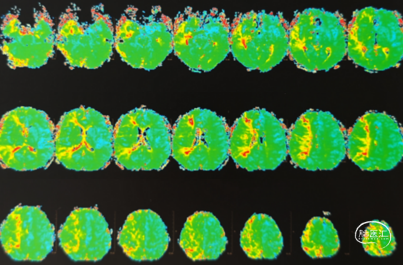

PWI(2024.11.07)

选对患者:中年男性,症状性颈内动脉非急性期闭塞。PWI示供血区明显缺血半暗带;手术指征明确。闭塞为B型,传统开通风险大,采用COSIS技术开通成功。